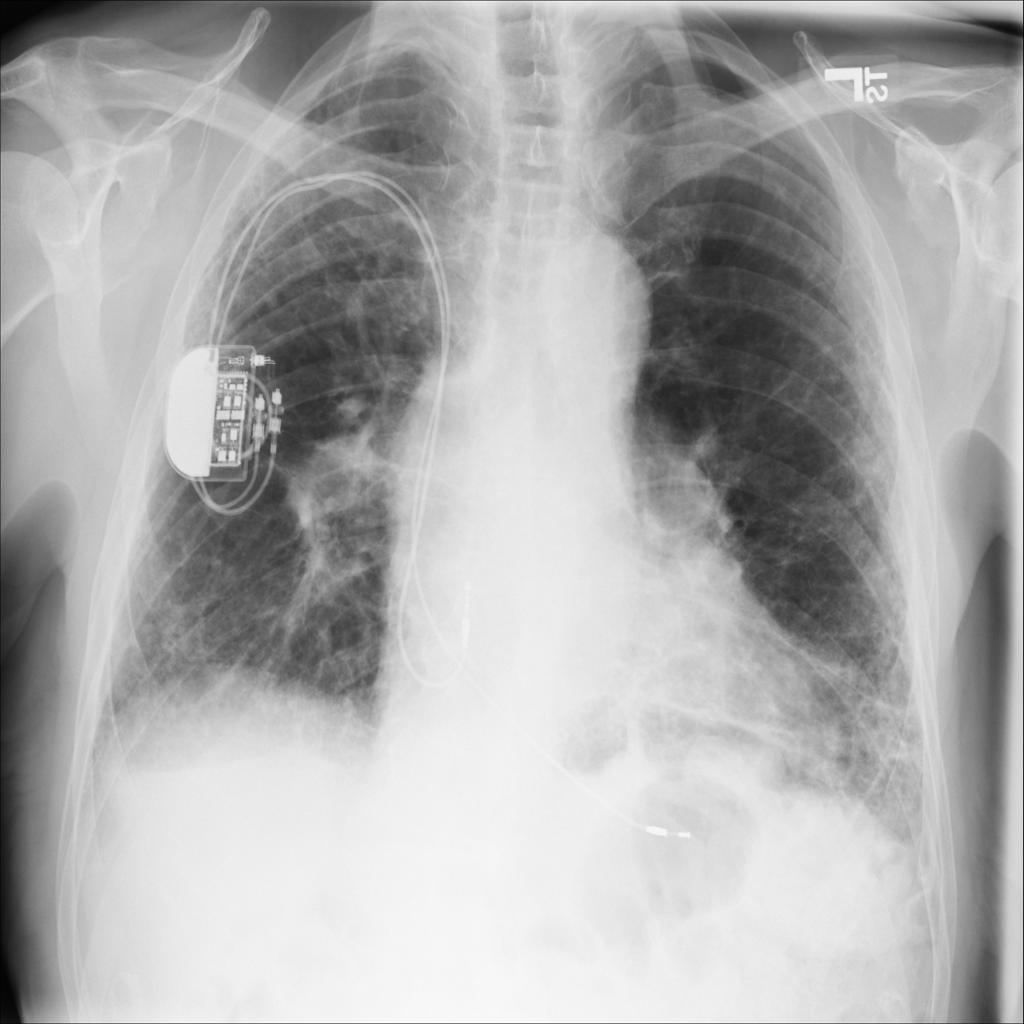

PAT-1F50 · IMG-000Fibrosis

PAT-1F50 · IMG-000

PA